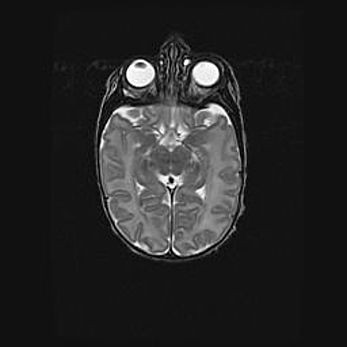

Церебральная ишемия II.

Возраст: 7 дней

Вес: 3350 г

Пол: женский

Окружность головы: 35 см

Срок гестации: 39 недель

Ишемия головного мозга – это состояние, которое развивается в ответ на кислородное голодание вследствие недостаточного мозгового кровообращения. У новорожденных она является следствием дефицита кислорода, что ведет к метаболическим расстройствам различной степени тяжести в тканях головного мозга, в том числе к развитию коагуляционных некрозов и гибели нейронов.